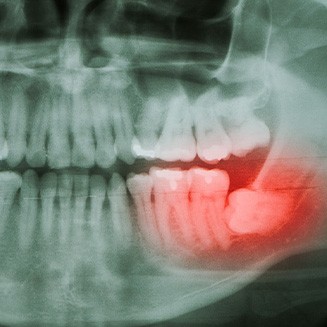

Why Do Wisdom Teeth Need to Be Removed?

You can usually count on our team to do everything we can to protect and preserve your natural teeth, leading many patients to wonder why wisdom tooth extraction is necessary. The truth is that these third molars tend to cause problems when they arrive which can put your dental health at risk.

We might recommend this treatment to address the following common concerns:

- If they become trapped in your jaw, they can form a cyst or infection that may require oral surgery to address.